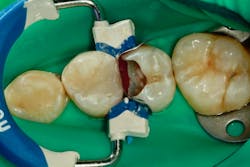

A rubber dam is applied and both lesions are prepared (figure 5).

After both teeth are prepared, we can see that these were large, deep lesions. An indirect pulp cap is placed over the pulp using a light-cured, flowable material (Theracal LC by Bisco) (figure 6).